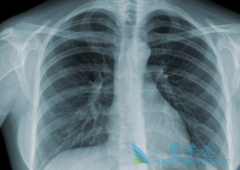

目前在中国,肺癌发病率在恶性肿瘤的首位,大约为46.08/10万,占所有恶性肿瘤19.59%。而且因为缺少前期发现的有用手法,大都病人在就诊时就已经是晚期。 肺癌晚期 的症状有哪些?据专家表示,肺癌患者中有5%-15%的不会出现明显症状,只有在做胸部影像检 ...

一说到癌症,大家都是非常恐慌的,毕竟以现在的科学技术来说,治疗癌症还是有一定的困难,对于每个人来说,癌症是非常可怕的一种疾病。而肺癌是发病率和死亡率增长最快,对人群健康和生命威胁最大的恶性肿瘤之一,男性肺癌发病率和死亡率占说所有恶性肿 ...

大家之所以害怕肺癌的原因是, 肺癌早期症状 非常不明显,这就导致很多患者被发现时已经是中晚期了,而且治疗的难度就比较大了,肺癌如果能在早期被发现,其实远没有大家想象的那么可怕。一般有数据显示肺癌患者如果能在早期被发现,一般五年生存率都能 ...

一般来说,肺癌是人们非常害怕的疾病,那么出现这八种情况,非常有可能是 肺癌早期症状 ,千万不能忽视!希望大家以后提高警惕,更关注自己的健康。一、胸闷,绝大部分的胸闷是感冒引起的,但是如果你最近没有感冒,也没有其他的病状的话,那么莫名其妙 ...